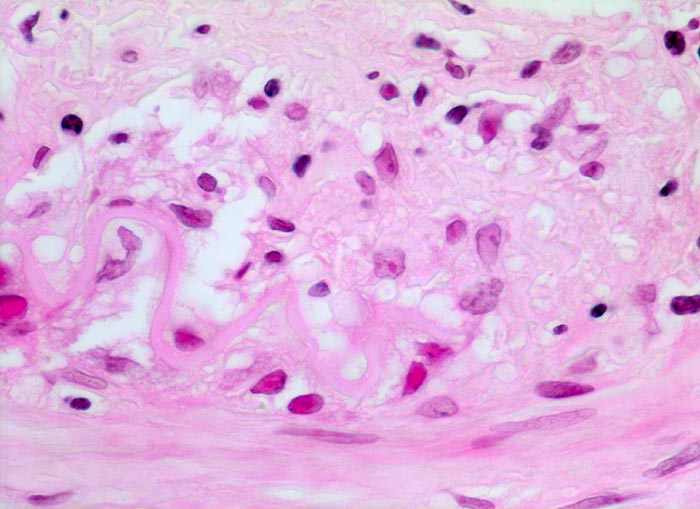

Histologisch diagnostisch ist der Nachweis von monohistiozytären Entzündungsinfiltraten entlang der Lamina elastica interna und deren Fragmentierung bzw. Zerstörung über längere Strecken (> 242). In frischen Läsionen findet sich die Entzündung unter Umständen ausschliesslich im Bereich der Vasa vasorum der Adventitia und der Media. In nur 50% der Fälle sind mehrkernige Riesenzellen (> 237) vorhanden. Seltenere Befunde sind eine Entzündung der Vasa vasorum, Verkalkungen der Lamina elastica, Intimaverdickungen und fibrinoide Gefässwandnekrosen. In Abwesenheit einer Entzündung lässt sich eine abgeheilte Arteritis temporalis nicht von atherosklerotischen oder unspezifischen altersbedingten Veränderungen der Arterie unterscheiden.

• Histiozyten und mehrkernige Riesenzellen finden sich bevorzugt entlang der Lamina elastica interna. Die Riesenzellen enthalten teilweise phagozytierte Fragmente der Lamina elastica interna.

• Ausgeprägte Intimafibrose mit mit dichten Infiltraten zerfallender neutrophiler Granulozyten.